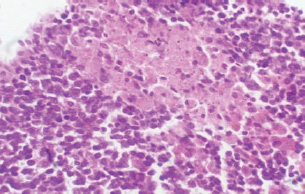

At 21 days post-infection, the lungs display moderate venous dilation and congestion, with abnormal leukocytes, indicating ongoing vascular compromise (Fig. 9). The liver showed necrotic changes in the fibrous capsule region, focal inflammatory cell infiltration, and intact hepatic cords, indicating sustained but localized damage (Fig. 10). The spleen exhibited plasma cell and macrophage proliferation within the red pulp, mild sinus dilation, and a few megakaryocytes, suggesting chronic immune activation (Fig. 11). The kidneys showed atrophic glomerular tufts and cystic dilation of adjacent tubules, indicating worsening renal pathology (Fig. 12). The mesenteric lymph nodes showed lymphoid follicles containing abnormal plasma cells and macrophages within the necrotic foci (Fig. 13).

Fig. 13. A histopathological section of the mesenteric lymph node of (G2) at 21 days postinfection showing a lymphoid follicle containing numbers of abnormal plasma cells and macrophages within necrotic foci (H&E stain X 40).